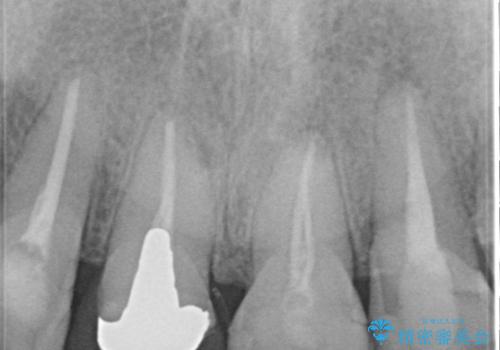

- 前歯の変色を主訴に来院されました。

歯茎のラインも整っていなかったため、手術を行いきれいな被せ物をいれることができました。

歯茎のラインを整える手術を行ったあとは、しばらく待ってから被せ物の治療を行っていきます。